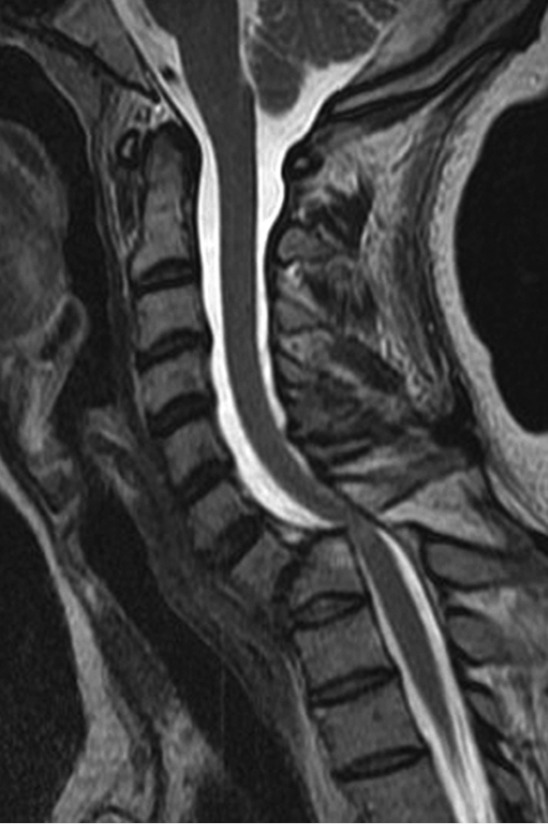

Figure 3.

Sagittal T2-weighted MRI confirms spinal cord signal change at the level of the spondylolisthesis. Complete disruption of ligamentous complex is also identified in the image.